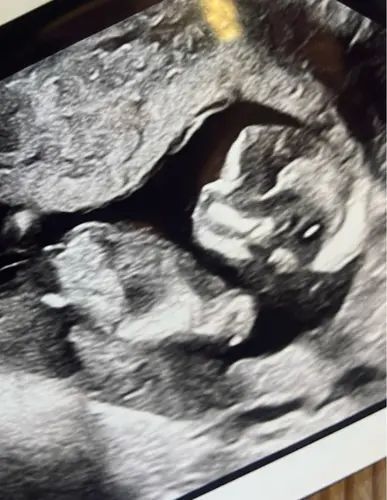

Wat denken jullie op basis hiervan? Ben wel benieuwddd. Ben zelf 13 weken

Meisje denk ik obv de voorbeelden en toelichting 😊